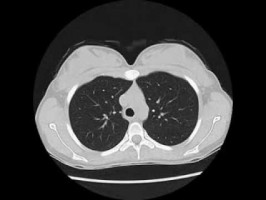

The article references a recent US Preventive Services Task Force recommendation that heavy smokers undergo a yearly screening for lung cancer.

"We are very happy about this Task Force recommendation and the approval of lung cancer screening as a benefit by CMS. Lung screening with low dose CT will save many lives by detecting lung cancer at earlier, treatable stages," Toll said.